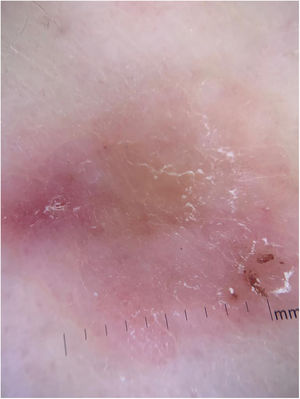

A 76-year-old patient complained an asymptomatic lesion for more than 6 months, consisting of a normochromic plaque on the lower back, somewhat papillomatous with a slightly erythematous center (Fig. 1), with peripheral white striae and microulcerations on dermoscopy (Fig. 2). Histopathological examination showed an epithelial basaloid proliferation with a focally reticulate pattern (Figs. 3 and 4). The excision of the lesion was performed.

It is more often reported in females (54%) and the elderly3 and is probably underreported. It presents clinically as normochromic/brown single or multiple lesions, such as papules or plaques, dome-shaped or sessile, which can mimic benign skin lesions that would not be routinely excised or biopsied, such as pedunculated fibroma, acrochordon, seborrheic keratosis, and dermal nevus.4,5 It affects non-photoexposed areas such as the lumbosacral and abdominal region, groin, and foot. On dermoscopy, thin branched vessels, punctiform vessels, white septal striae, corneal pseudocysts, and ulcerations are observed. Some lesions show structureless gray-brown pigmentation and bluish-gray dots.6